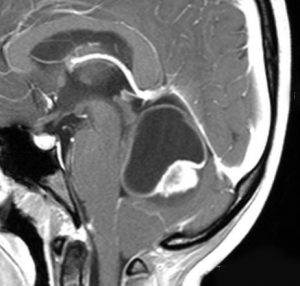

18歳で発症して,60歳まで無治療の大きな視床下部毛様細胞性星細胞腫

hypothalamic pilocytic astrocytoma

1968年 18歳の時に頭痛嘔吐で発症しました。第3脳室腫瘍と閉塞性水頭症の診断だけで,シャント手術を受けました。手術も化学療法も放射線治療もされていません。下の画像は60代で撮影されたものです。この例では,第3脳室内に増大した大きな毛様細胞性星細胞腫が,視床下部下垂体障害を出すことなく,自然経過で増大停止 growth arrest して,カチカチに固まってしまうということを教えてくれます。でも,こんなに都合よく経過観察できる例も珍しいです。

CTでは強い石灰化があります。右のT2強調画像では腫瘍は等信号,視交叉の後ろにあります。内部の低信号は石灰化です。

T1強調画像では等信号,ガドリニウム増強でごく一部がまだらに増強されます。